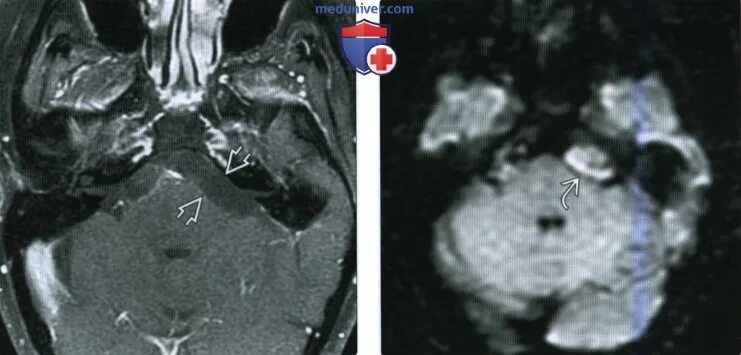

Мрт головного мозга мосто мозжечкового угла